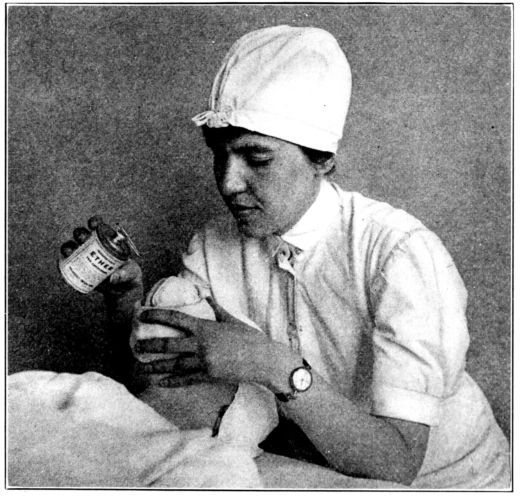

| 103. | Giving chloroform for obstetrical anæsthesia | 287 |

| 104, 105. | Giving ether for obstetrical anæsthesia | 289, 290 |